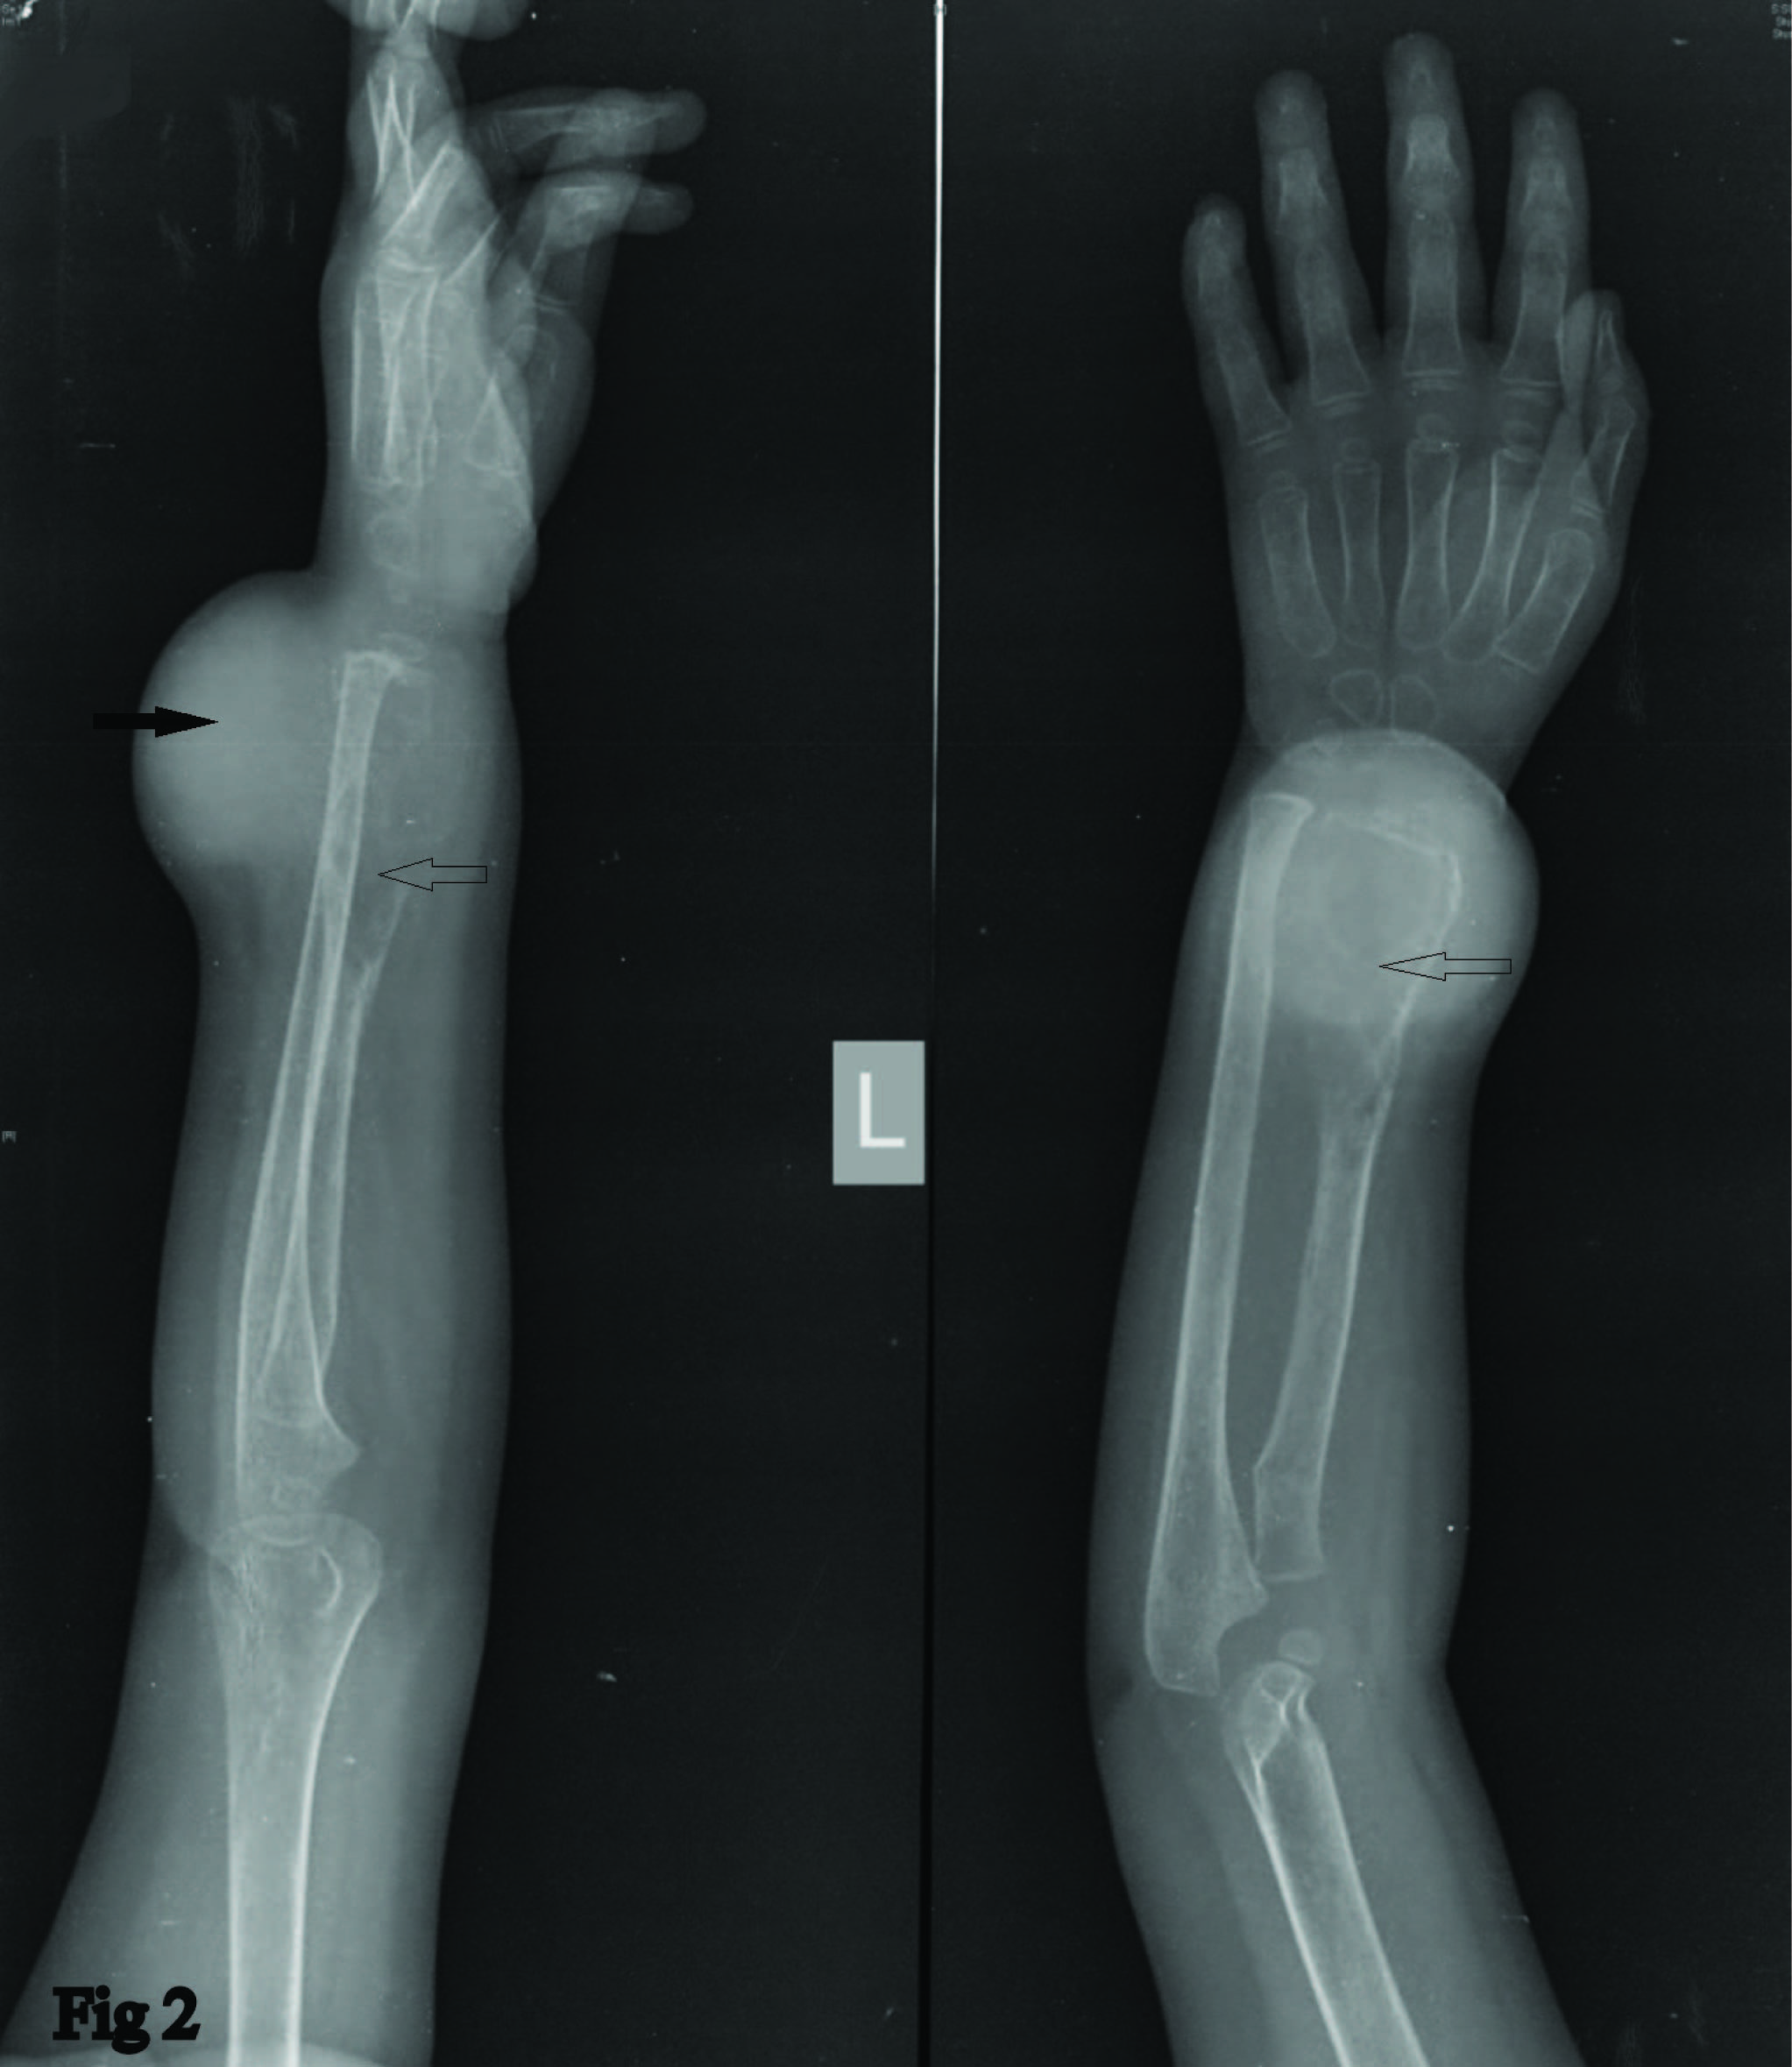

A 3-year-old female child reported in bone and soft tissue unit of Tata Memorial Hospital, Mumbai with a painful swelling of left distal forearm for a duration of two months, which was progressively increasing in size over the period of one month without any detrimental impact on health of the patient. There was no history suggestive of trauma or underlying systemic disease. Consent for examination, investigation and subsequent management was taken from the parents of the patient. Clinical examination revealed a swelling 4 x 3.5cm in dimensions, dorsally extending from distal one third of forearm up to the wrist joint with well defined margins, a firm consistency and tenderness on palpation. Swelling was fixed to underlying structures. Overlying skin was stretched and ulcerated [Table/Fig-1]. Finger and wrist extension was painful and restricted. X-rays revealed a lytic-destructive lesion, thinned out cortices, blown out appearance and a wide zone of transition. Adjacent soft tissue component was noted on dorsum of distal radius [Table/Fig-2].

Radiograph showing bony lesion distal radius (arrow) with soft tissue component (solid arrow)